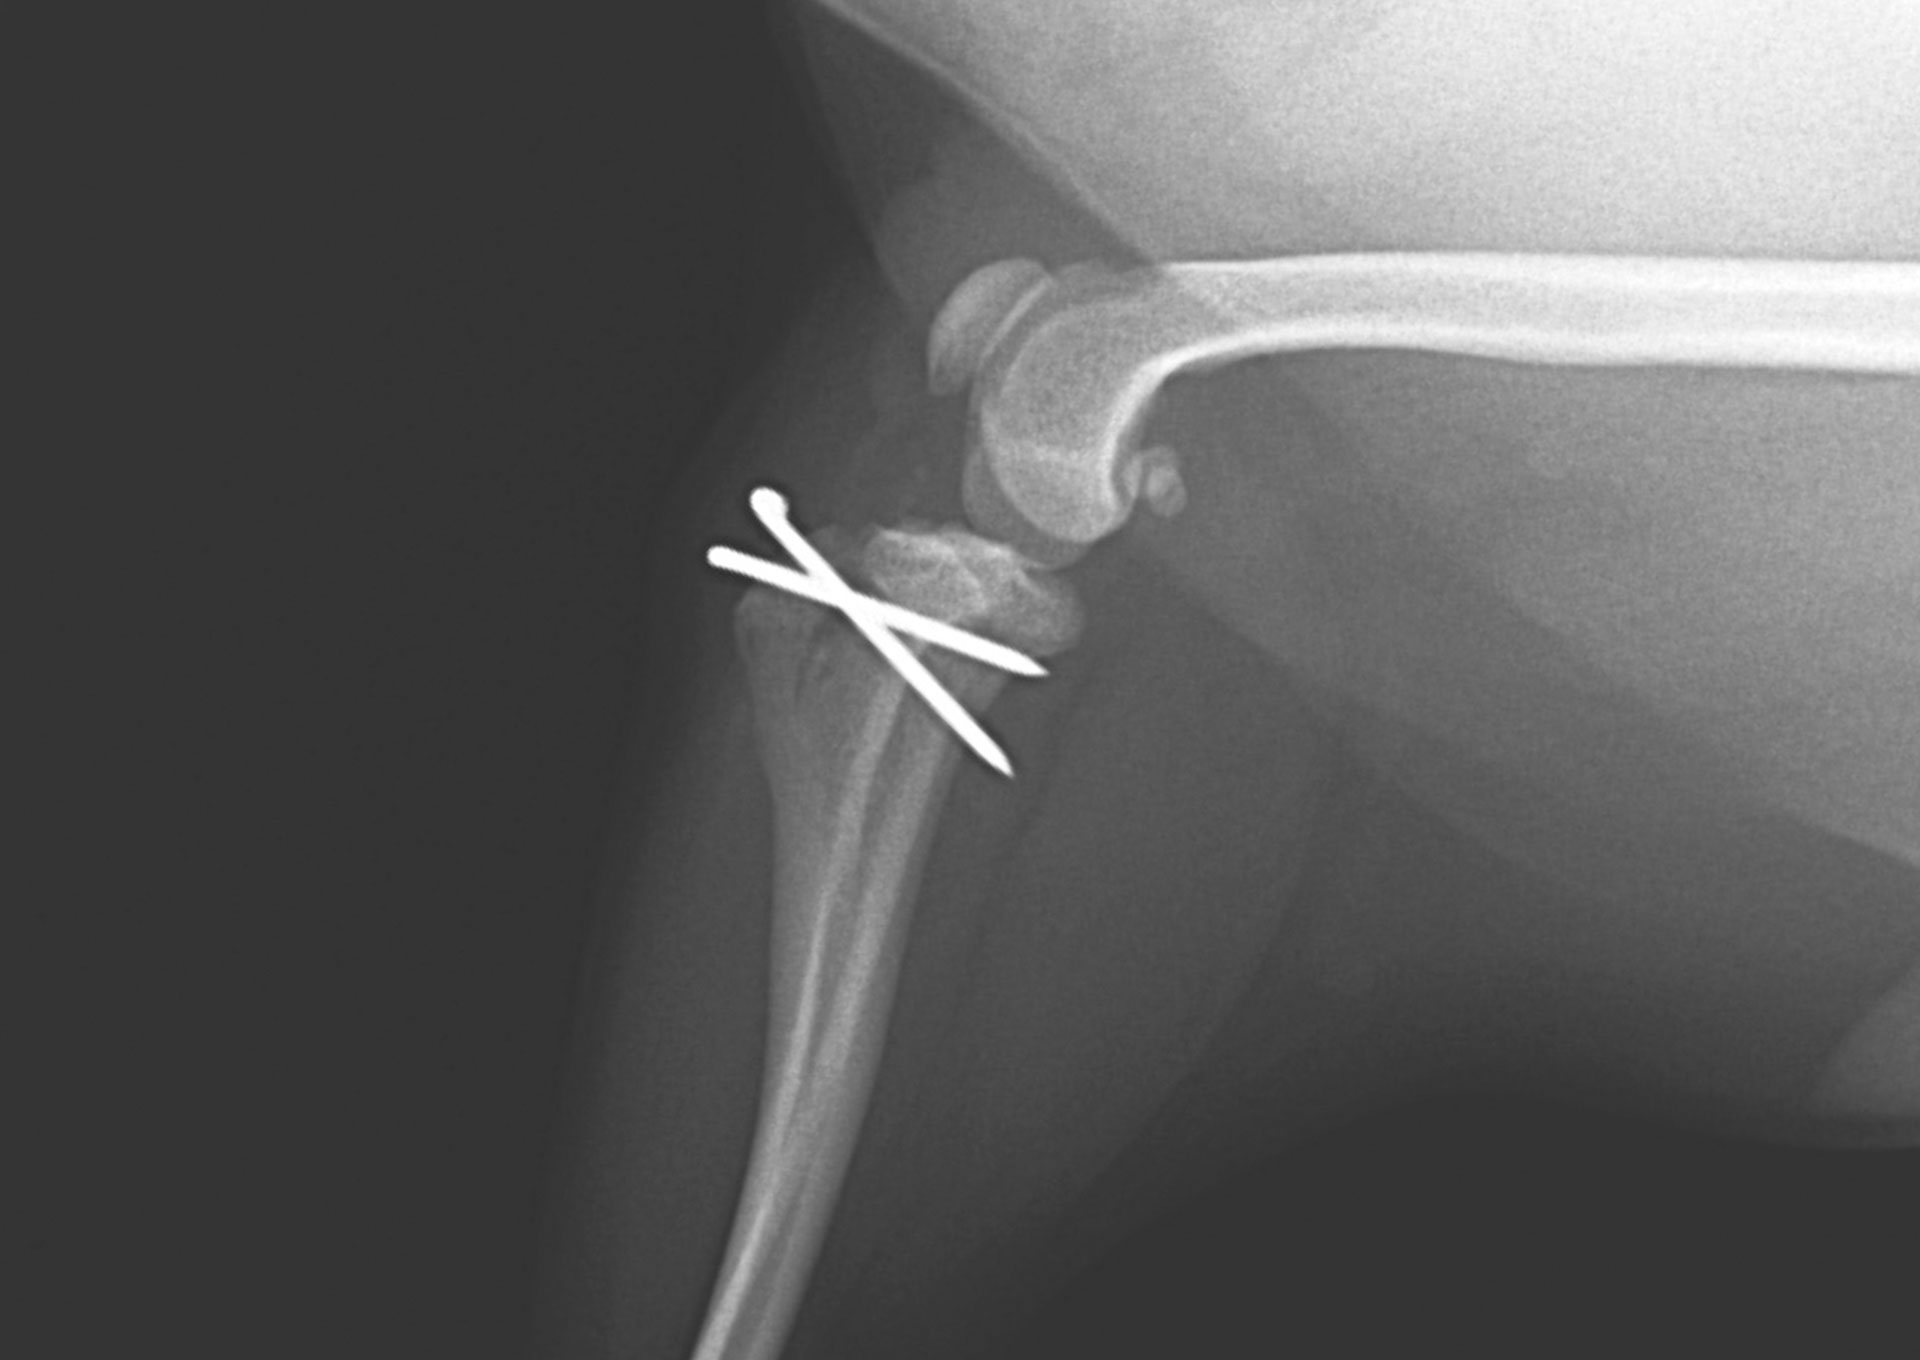

膝蓋骨脱臼の外科治療

膝蓋骨脱臼は小型犬に多くみられる疾患で、症状の程度に応じた適切な外科治療が重要となります。

当院では、膝蓋骨脱臼に対する外科治療を数多く行ってきました。

これまでに200症例以上の手術実績があり、重症度や骨格の状態に応じて、適切な術式を選択しています。

特に小型犬の症例にも多く対応しており、術後の安定性や再発防止を見据えた手術を心がけています。

歩行機能の回復と、その後の生活の質を大切にした治療を行っています。